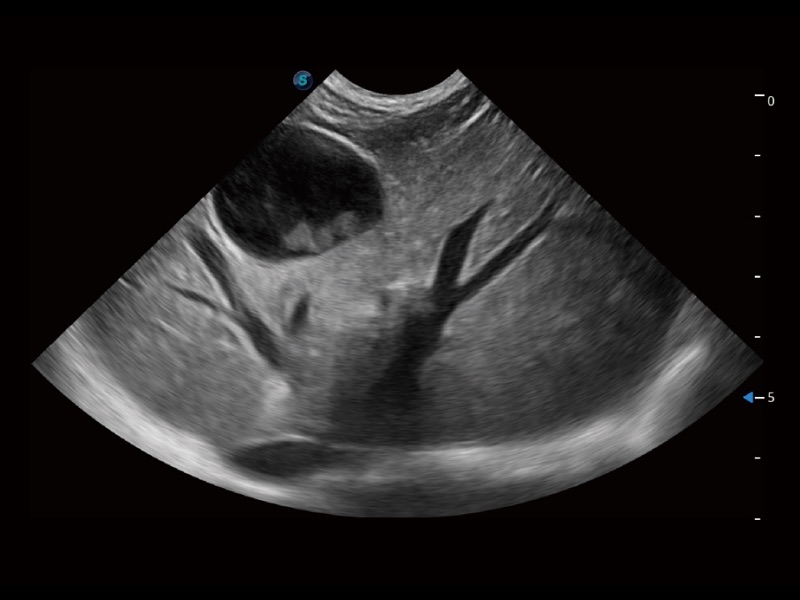

猫、中小型犬及小型异宠动物

ProPet 70 进一步提升了微米成像算法,更加注重对基础原始图像的还原和保留,在有效减少斑点噪声、增强组织边界显示的同时,避免过度优化丟失真实的解剖信息。

ProPet 70专为动物医生设计,对不同的动物体型和生理结构作出了针对性的优化。通过动物影像专用软件,可满足个性化的应用需求,帮助动物医生获得更精确的诊断数据。

为精细结构及组织边缘提供高清晰度的图像和更大的成像视野。帮助减轻医生的用眼疲劳,快速精准获得测量的数据。